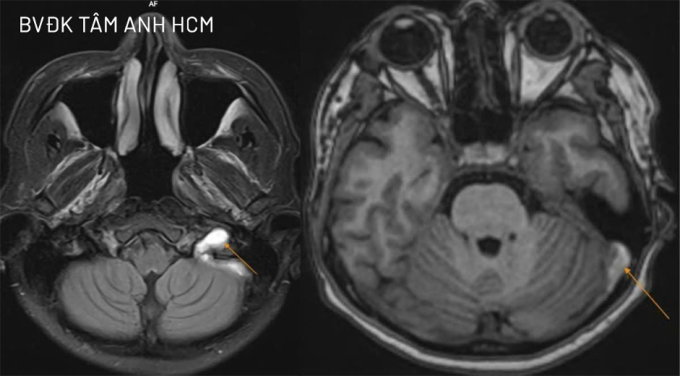

BS.CKI Cao Hoàng Trọng, Khoa Thần kinh, Trung tâm Khoa học Thần kinh, Bệnh viện Đa khoa Tâm Anh TP HCM, cho biết chị Mai tỉnh táo, không nói đớ, không yếu liệt tay chân, không co giật. Kết quả chụp MRI 3 Tesla khảo sát mạch máu não người bệnh cho thấy cục máu khối hình thành ở tĩnh mạch cảnh trong bên trái, làm tắc nghẽn dòng máu tại đoạn hành. Huyết khối đang ở giai đoạn bán cấp và đã lan lên xoang sigma, một phần xoang ngang bên trái.

Ảnh MRI cho thấy cục huyết khối gây bít gần như hoàn toàn tĩnh mạch cảnh trong trái, lan các xoang tĩnh mạch lân cận. Ảnh: Bệnh viện Đa khoa Tâm Anh